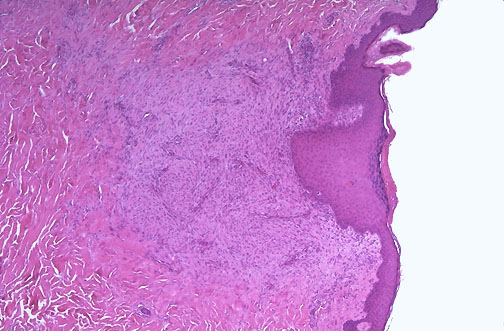

| This is a healing biopsy site on the skin seen a week following the excision, The skin surface has re-epithelialized, and below this is granulation tissue with small capillaries and fibroblasts forming collagen. After a month, just a small collagenous scar will remain. |